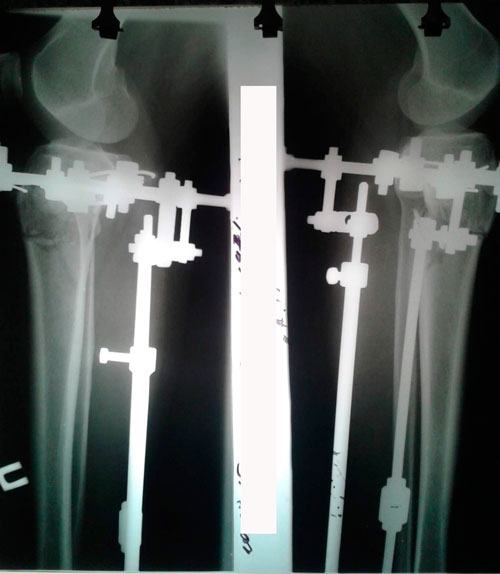

РЕНТГЕН ДО ОПЕРАЦИИ